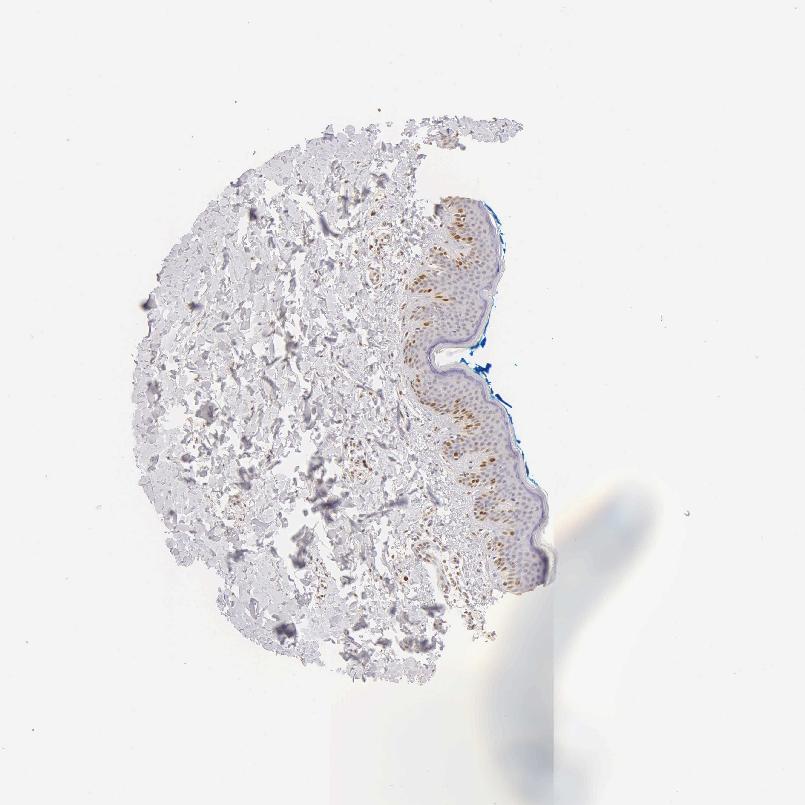

SKIN 2 - Antibody stainingi

Antibody staining in the annotated cell types in the current human tissue is reported as not detected, low, medium, or high, based on conventional immunohistochemistry profiling in selected tissues. This score is based on the combination of the staining intensity and fraction of stained cells.

Each image is clickable and will lead to virtual microscopy that enables deeper exploration of all samples and also displays staining intensity scores, fraction scores and subcellular localization as well as patient and tissue information for each sample.

Antibody HPA000451Antibody HPA001164Antibody CAB000058Antibody CAB068198Antibody CAB080228

Arrector pili muscle cells --Not detected--

Cells in basal layer --High--

Cells in corneal layer --Not detected--

Cells in granular layer --Not detected--

Cells in spinous layer --Medium--

Endothelial cells --Not detected--

Epidermal cells MediumLow-LowMedium

Extracellular matrix --Not detected--

Fibrohistiocytic cells --Medium--

Langerhans cells --Not detected--

Lymphocytes --High--

Melanocytes --Not detected--

Vascular mural cells --Not detected--